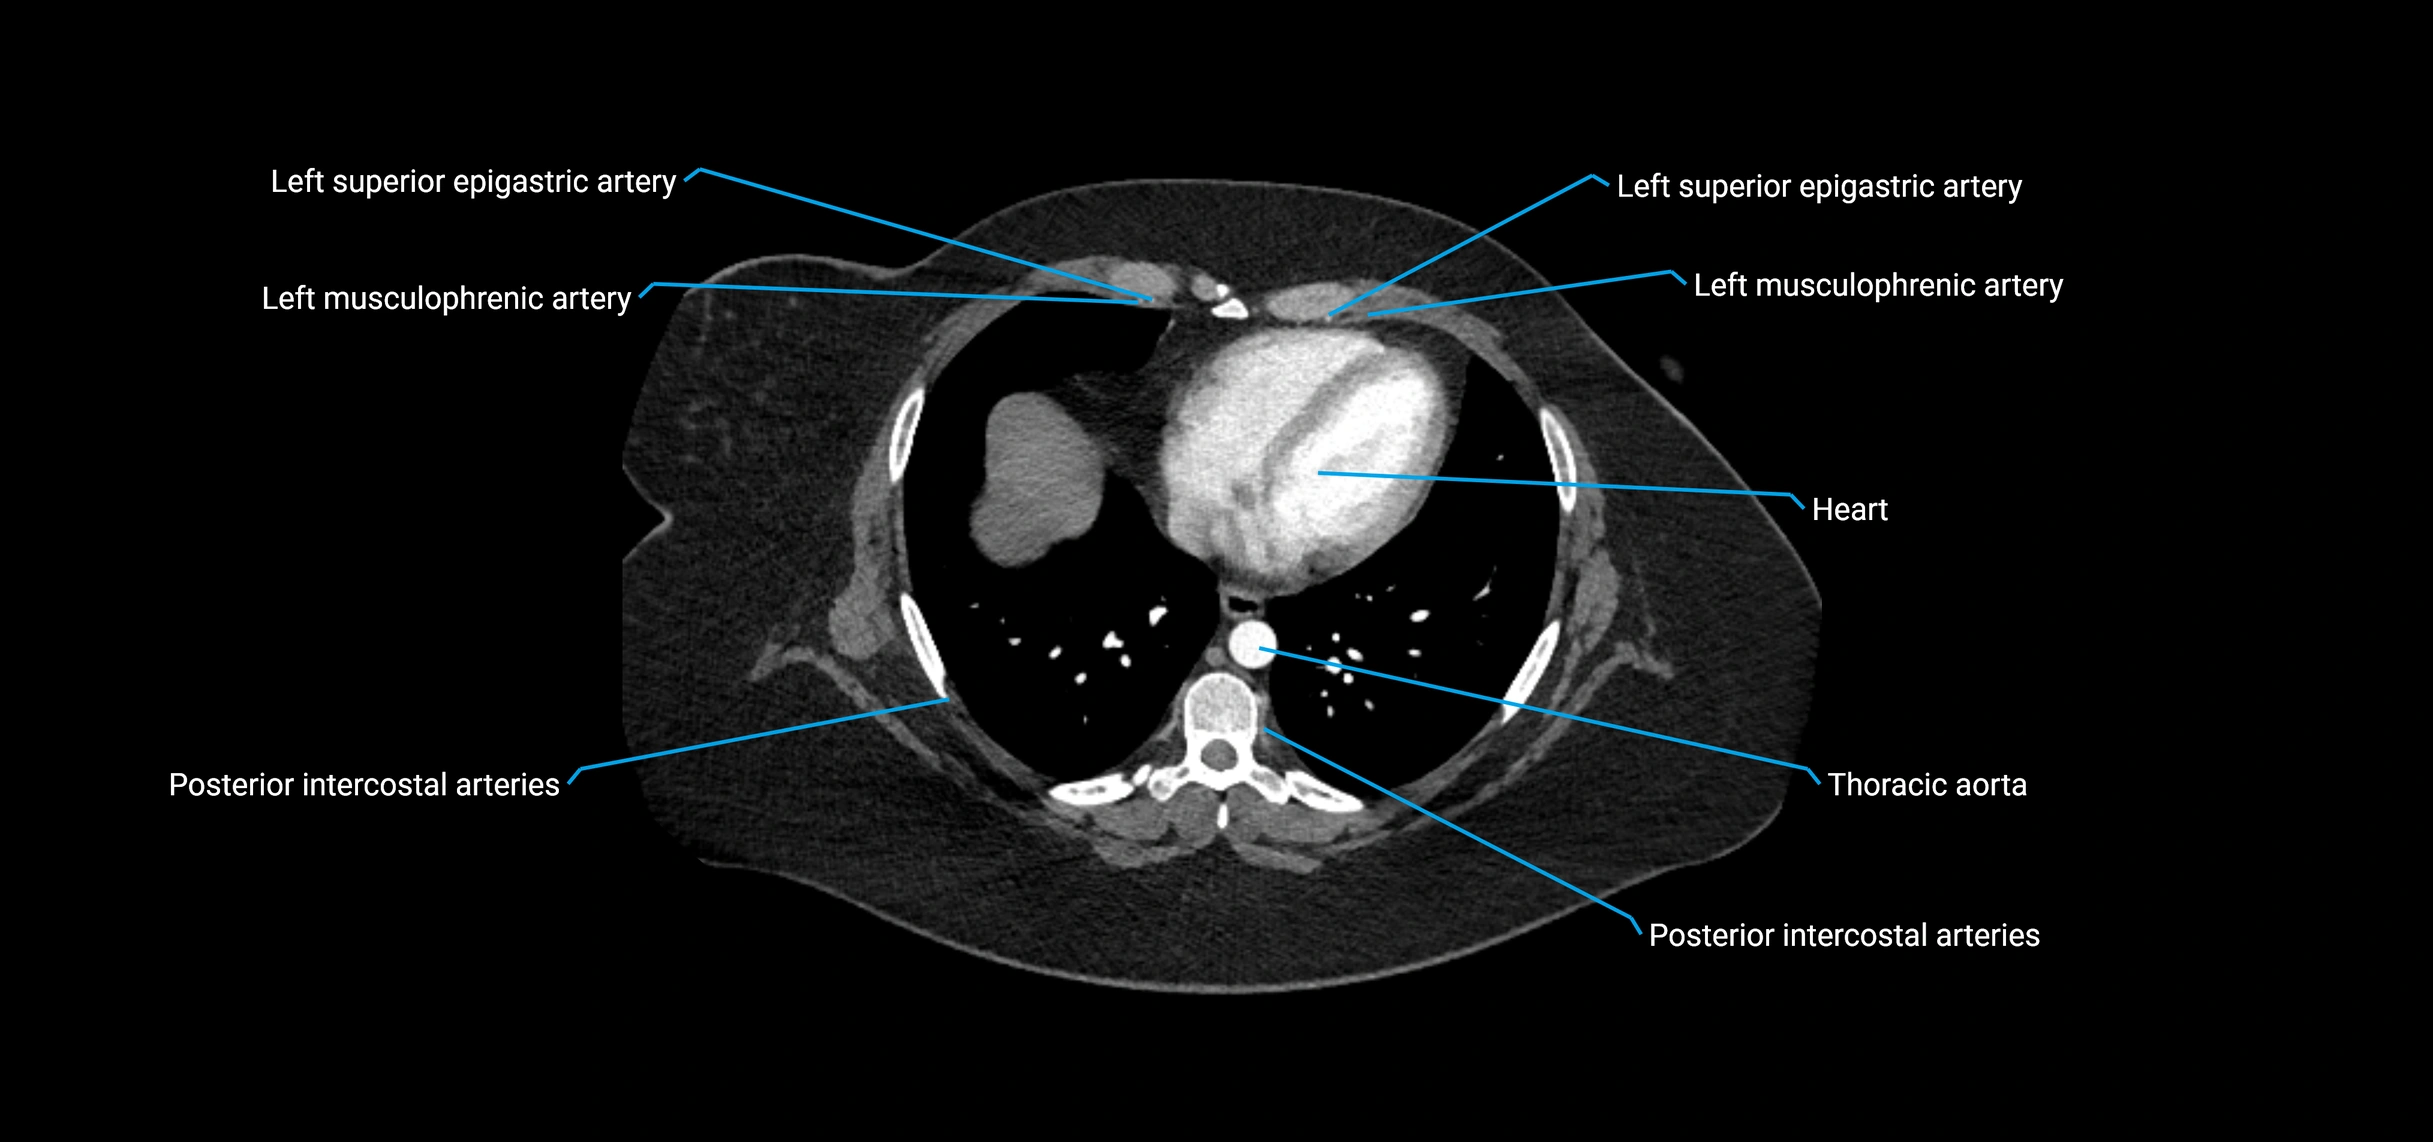

CT images

image

Contrast-enhanced CT (CTA):

• Gold standard for abdominal aortic imaging

• Provides excellent detail of lumen, wall, aneurysm, thrombus, and branch vessels

• Multiplanar and 3D reconstructions help in aneurysm measurement, stent graft planning, and dissection evaluation